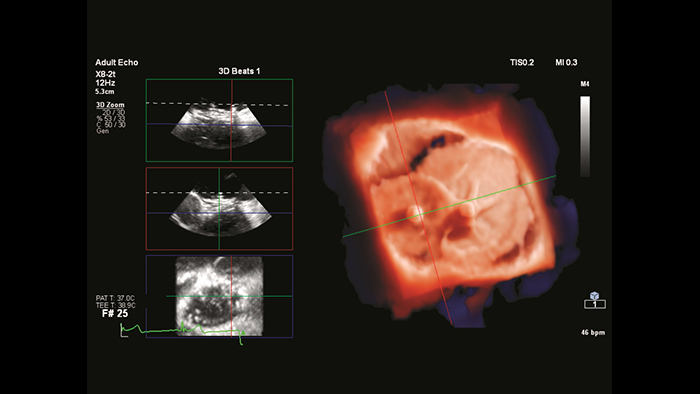

Deep insights with TrueVue color and GlassVue

Cardiac TrueVue photorealistic rendering with MultiVue image alignment

EchoNavigator heart model segmentation